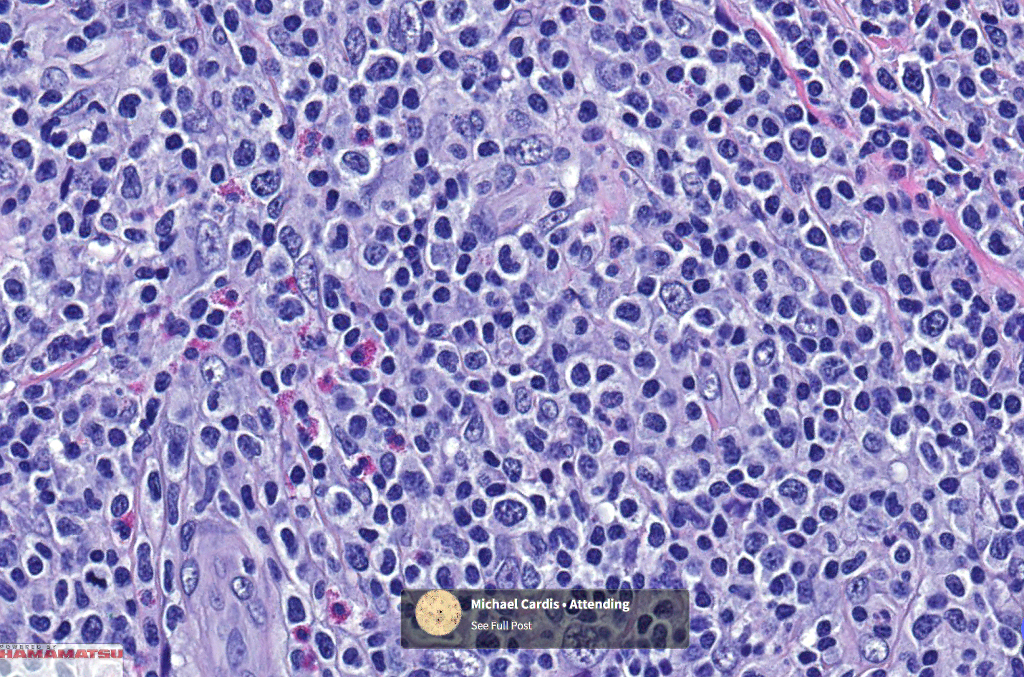

•Type A: 75-80%, wedge shaped infiltrate with base uppermost, large, anaplastic cells with abundant cytoplasm and vesicular nuclei containing prominent nucleoli, can resemble Reed-Sternberg cells, conspicuous mitoses & background infiltrate of lymphocytes, plasma cells, histiocytes, neutrophils & eosinophils